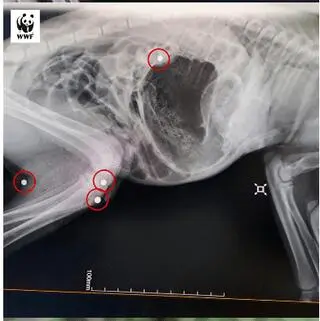

Jak przekazuje WWF Polska, na pierwszy rzut oka nie było widać ani śladów krwi, ani ran wlotowych. Jednak podczas sekcji zwłok weterynarz odkrył w ciele rysia kulki śrutu – w tym w kręgosłupie. O sprawie została powiadomiona policja – ryś jest gatunkiem objętym ścisłą ochroną.

W ciele kotki odnaleziono śrut

Źródło: WWF Polska